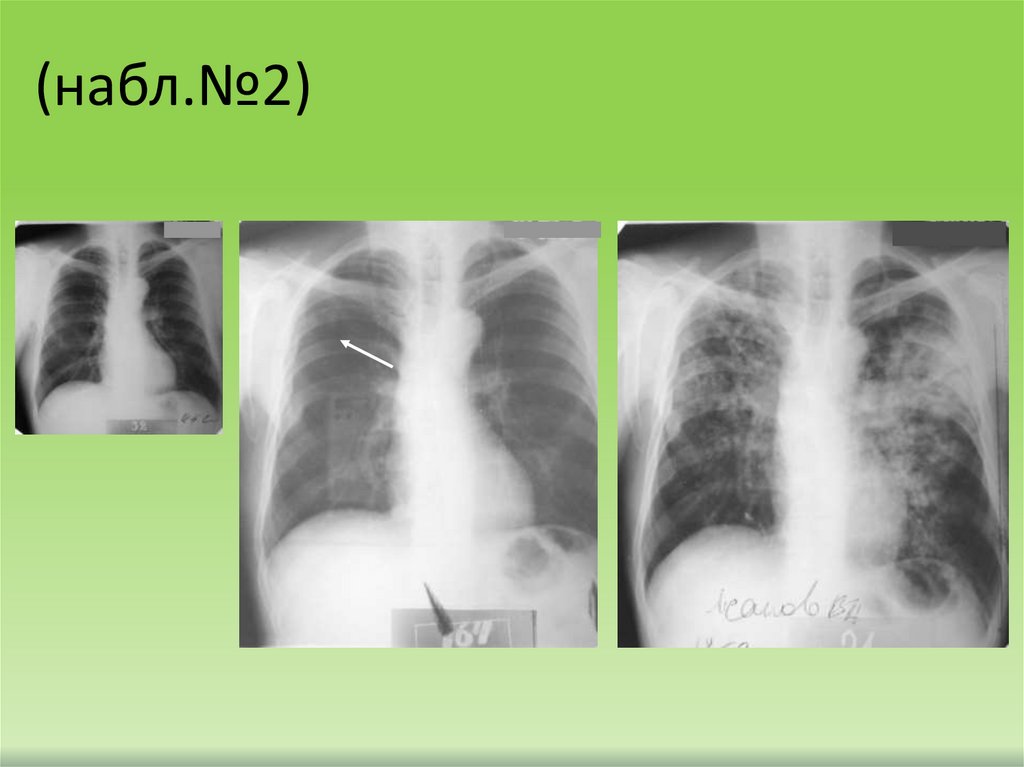

(набл.№2)